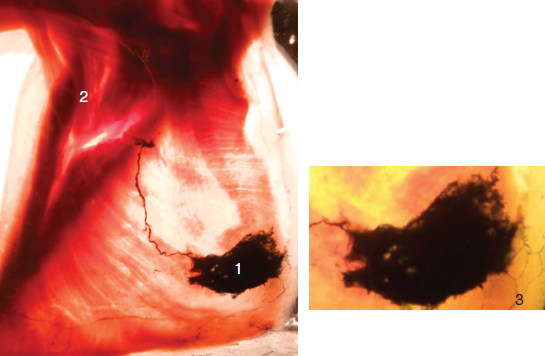

The axillary pedicle is the largest of the three mammary lymphatic pedicles; it is formed by two to six lymphatic vessels. This pedicle may receive lymph vessels from any breast quadrant, either superficial or deep, from the nipple, areola, or the skin covering the breast. It emerges from the lateral region of the breast, following the border of the pectoralis major, passes to the base of the axilla, and then crosses the pectoroaxillary aponeurosis (Fig. 6-7).

FIG. 6-7 1, Breast area; 2, axillary lymph nodes; 3, axillary lymphatic pedicle. Inset: Closeup view.

Four pedicles secondary to the axillary pedicle can be identified:

1. Lateral mammary: The lateral mammary pedicle follows the path taken by the lateral mammary vessels. It is formed by two to five lymphatic vessels and joins the nodes in the lateral mammary chain. This is the first node level of the axilla.

2. Subscapular: The subscapular pedicle is little developed. It passes toward the posterior surface of the axilla, where the subscapular vessels lie. It consists of one or two lymphatic vessels and joins the nodes in the subscapular chain.

3. Superior thoracic: The superior thoracic pedicle is formed by a single lymphatic vessel that crosses the aponeurotic base of the axilla, passes toward the apex of the axilla, and then slips in front of the anterior serratus and behind the pectoral muscles, to end in the superior thoracic chain. It is the second node level of the axilla.

4. Axillary-vein: The axillary-vein pedicle occurs least frequently. It is so named because it passes directly into the highest part of the axillary space and lies in direct contact with the axillary vein.